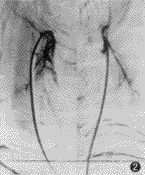

图2 聚乙烯醇微球栓塞后造影见原增粗的甲状腺上动脉及其分支动脉已闭塞,腺体染色消失

1.介入栓塞治疗的方法:应用Seldinger技术,在数字减影X线机(Philips 2000或Toshiba V 8 000)的监测下,选择性行双侧甲状腺上、下动脉插管并造影,明确甲状腺上、下动脉位置及甲状腺的血供情况。每条甲状腺动脉在栓塞前先推注地塞米松3~5 mg,然后缓慢向双侧甲状腺上动脉或加一侧甲状腺下动脉注入暂时性(明胶海绵)或永久性[白芨微球或聚乙烯醇(polyvinyl alcohol,PVA,美国Cook公司生产),微粒直径为150~400 μm]的栓塞剂,透视下观察甲状腺动脉栓塞情况,直至细小动脉血供中断为止,术中注意栓塞剂的返流。随后用带羊毛不锈微弹簧钢圈(Cook公司生产)栓塞甲状腺上、下动脉主干。再次造影,以确定甲状腺血管已被完全栓塞(图1,2)。栓塞术后给予抗生素及强的松(15 mg/d)3~7 d,停用或减少抗甲状腺药物,定期复查甲状腺机能。